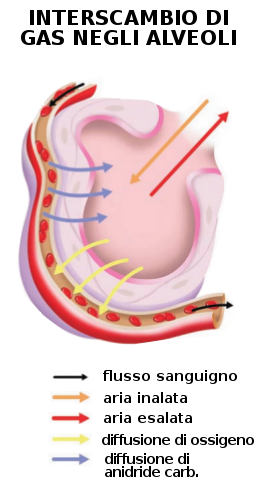

Ematosi e respirazione cellulare

L'ematosi consiste nell'interscambio gassoso tra il sangue e l'aria alveolare. I capillari sanguigni (ramificazioni delle arterie polmonari) giungono agli alveoli polmonari con sangue carbossigenato. I gas attraversano gli epiteli polmonari e i capillari per diffusione passiva, ovvero passano dal luogo a maggior concentrazione a quello a minore concentrazione:

- nell'alveolo il diossido di carbonio è meno concentrato che nel sangue e per questa differenza di concentrazione, passa dal sangue all'alveolo polmonare;

- l'ossigeno è più concentrato nell'alveolo che nel sangue, per cui passa dall'alveolo al sangue.

- Il sangue che giunge a ciascun alveolo per mezzo dei capillari arteriosi (ramificazioni della arteria polmonare) è carico di anidride carbonica (povero di ossigeno).

- L'aria alveolare è ossigenata (povera di CO2).

- Per diffusione l'ossigeno passa dall'alveolo al sangue dei capillari venosi e, successivamente, attraverso le vene polmonari giunge al cuore che lo spinge a tutto il corpo.

- Per diffusione, l'anidride carbonica passa dai capillari arteriosi all'alveolo, poi attraverso le vie aeree risale all'esterno durante l'espirazione.